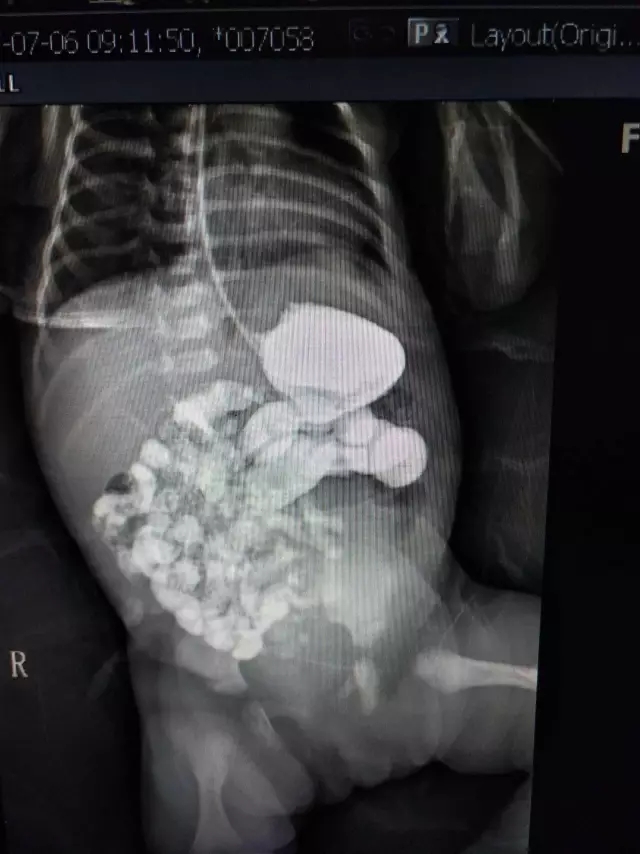

通过消化道造影检查,造影显示患儿空肠上段狭窄,是先天性的消化道畸形,具体情况必须对患儿进行剖腹探查术才能确定。经肠探查发现新生儿是肠扭转,要进行新生儿肠扭转手术复位。